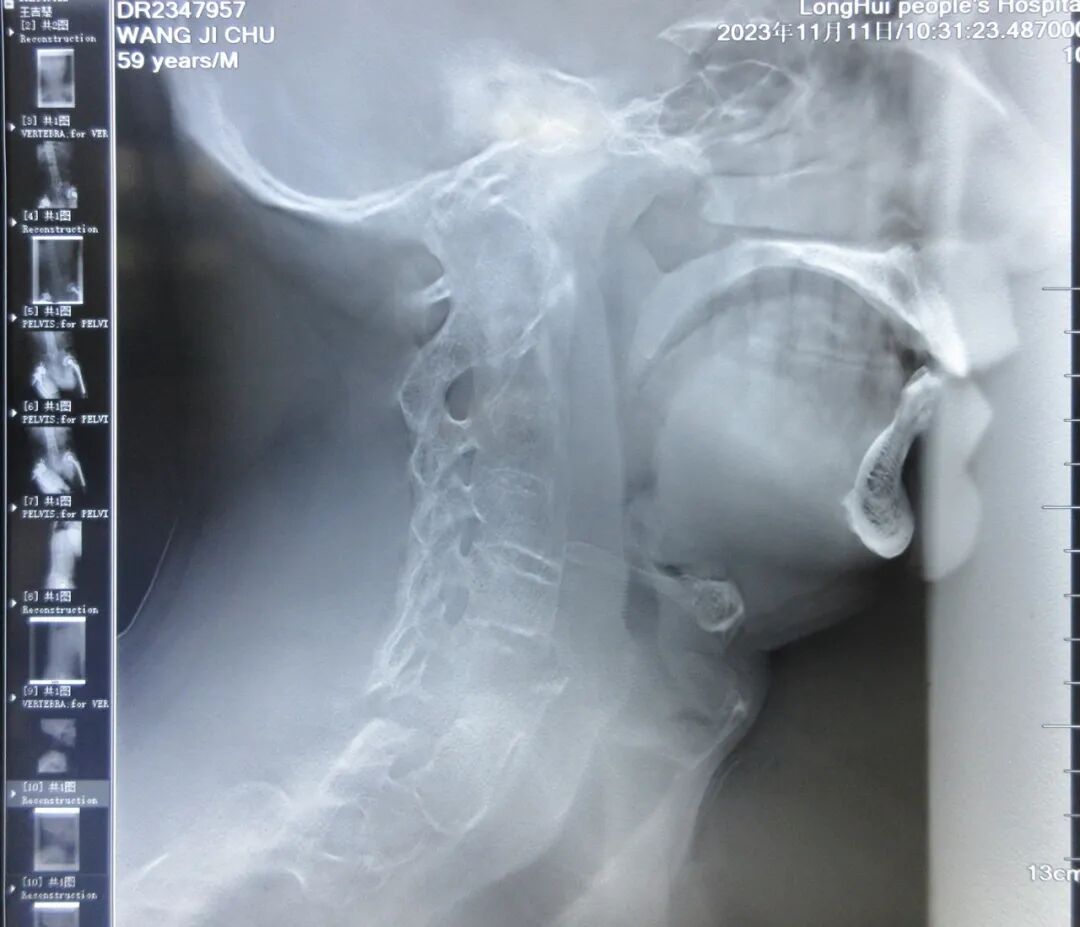

事情还要从今年的4月26日说起,那天司法鉴定所接待了一位特殊的访客——隆回县退役军人事务局领导来到我所咨询:患者王某某,61岁,系隆回县军队离退休干部修养所管理的军队退休干部,因病致瘫在床无法出门、生活十分困难!问能否提供上门服务?

对王某某同志评估护理依赖程度,司法鉴定所戴建华主任详细查阅其病历及影像学资料,得知王某某患有强直性脊柱炎,颈6椎体爆裂骨折伴脊髓损伤,颈7椎体附件骨折,双髋关节置换术后,次日戴建华主任带领法医蒋琴丹随同退役军人事务局领导来到王某某家中对其进行体查——只见患者呈颈强直状态,双大腿背侧见大面积压疮,双下肢屈曲畸形、关节僵硬等,穿衣、修饰、洗澡、床椅转移、行走、大小便、如厕均不能完成,最终评估其为完全护理依赖。